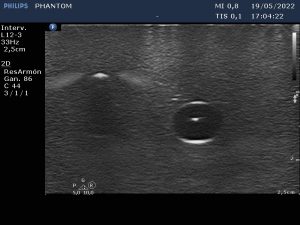

És per això que aquest mes de juny ha arrencat amb un ‘Curs de punció ecoguiada i dispositius d’accés vascular’, al Consell Comarcal de l’Alt Urgell, impartit per tres infermers, que a més són tècnics superiors en Imatge pel Diagnòstic, membres de l’Equip de Teràpia Intravenosa (ETI) de l’Hospital Universitari Arnau de Vilanova (HUAV) de Lleida. La punció ecoguiada és una tècnica gens invasiva que permet a la infermera veure, de forma clara i directa, l’estructura vascular a la qual ha d’accedir i col·locar l’agulla en el lloc més adient per inserir la via (catèter) o qualsevol altre dispositiu d’accés vascular (DAV), evitant incomoditats i complicacions pel pacient.

Amb aquest curs, el COILL pretén millorar la qualitat i atenció de les infermeres de les comarques pirinenques introduint-les en el Mètode RaPeVA, un mapeig venós en diversos passos establerts de forma lògica i progressiva per analitzar les estructures internes del braç, descartar les zones de risc, determinar el lloc més apropiat de punció i assegurar-se la viabilitat de tot el recorregut del catèter.

La col·locació de catèters intravenosos i altres dispositius d’accés vascular –perifèric curt, de línia mitjana, central d’inserció perifèrica (PICC) o d’inserció central (CVC)– requereix expertesa i tècnica de la infermera, tant en la punció com el manteniment. La tècnica Seldinger, metodologia concebuda inicialment per a la cateterització percutània dels vasos sanguinis, però molt estesa en l’actualitat per l’alt nivell d’evidència sobre la seva utilitat que rau en la reducció de l’índex de fracàs en la col·locació de les vies centrals, així com de les complicacions afegides; o el rentatge intraluminal ‘Push-Stop-Push’ amb pressió positiva, que recomana la instil·lació dels catèters PICC amb sèrum salí fisiològic a embolades, per generar turbulències i garantir la neteja de les parets del dispositiu, com a tècnica de manteniment; han estat altres dels temes tractats.